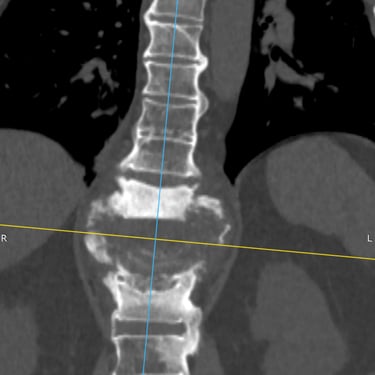

🧠Compresión medular cervical y dorsal: tratamiento mediante artrodesis y descompresión nerviosa.

La compresión medular cervical y dorsal es una patología grave que puede ocasionar déficit neurológico progresivo. La descompresión quirúrgica asociada a artrodesis vertebral permite liberar la médula espinal y estabilizar la columna, mejorando la función neurológica y evitando el deterioro clínico en pacientes adecuadamente seleccionados.